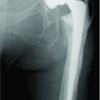

A 70-year-old man with a history of avascular necrosis left hip secondary to a post-traumatic femoral neck fracture, treated with failed cancellous screw fixation, presented 6 years after uncemented MoP THA. He reported progressive worsening of pain over the past 6 months in his left hip, leading to increasing difficulty in ambulation and eventual wheelchair dependence. The pain reportedly worsened following a fall at home 6 months before the presentation. His medical history included hypertension, which was well-managed with medication. Notably, he did not develop any symptoms suggestive of systemic metal poisoning. The patient’s prior THA, performed through a posterior approach, achieved a satisfactory outcome with pain-free ambulation until August 2018 (6 months pre-presentation). Following the fall, he developed progressive discomfort and instability in the hip. On clinical examination, the left hip was unstable with intermittent subluxation, readily reducible with traction, and had a constrained and painful range of motion. The surgical scar appeared well-healed without any erythema, sinus formation, or other concerning skin changes with no local rise in temperature. Standard laboratory tests, including erythrocyte sedimentation rate and C-reactive protein, returned results within normal limits. Pelvic radiographs demonstrated upper and outer migration of the head of the femur and downward displacement of the acetabular cup with metallic fragments (Fig. 1). No evidence of femoral stem loosening was observed. A computed tomography (CT) scan was performed but deemed inconclusive, suggesting liner failure, acetabular cup fracture, and radiodense opacities surrounding the hip joint. Magnetic resonance imaging (MRI) was not obtained due to the non-availability of metal artifact suppression techniques at the institute. The patient was posted for revision surgery based on clinical and radiographic findings. The revision surgery was performed using the posterior approach, just as in the primary surgery.